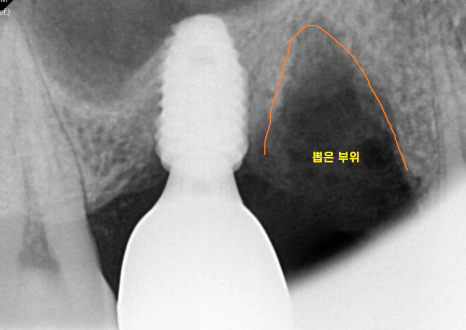

240729

임플란트 완성한 모습입니다.

잇몸 내려감으로 뼈가 꺼져있었기에

회복에 집중했습니다.

부족한 부분은 뼈이식을 통해 보충

원상태로 복귀시켜드렸습니다.